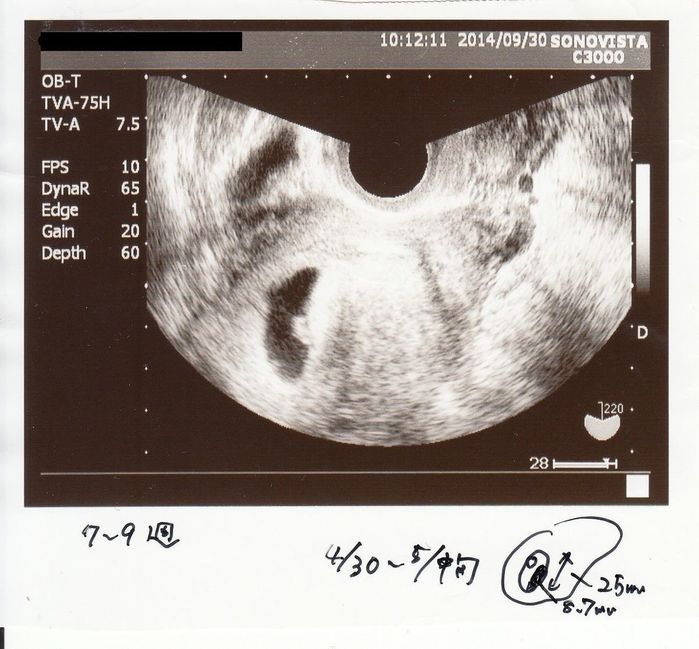

無事に胎嚢と心拍を確認 - 妊娠7週目のエコー写真

しばらく生理が来ないなと思って、妊娠検査をしたら陽性。1週間ほど経って都合のよい日に、上の子を出産した産院に行きました。左下の黒い丸が胎嚢、その中の小さな白いものが赤ちゃん。まだ胎芽と呼ばれる状態です。妊娠確定! エコーで胎嚢と心拍を無事に確認できたので安心しました。私も夫も3人兄弟。できれば子どもは3人欲しかったので、とても喜ばしい出来事でした。